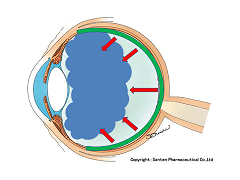

黒目(角膜)から入ってきた光は、目の奥の方のフィルム(網膜)に当たります。網膜は一つの束(視神経)になって、最終的には脳ミソにつながり、「物が見える」という事になります。

図の赤矢印の部分は視神経乳頭と言って、網膜が集まって束になる部分なのですが、実はこの部位のみ光を感じ取ることはできないのです。

写真だと水色の部分が視神経乳頭(マ盲点)になります。ちなみに、物を見る中心部の網膜は黄斑と呼ばれ、オレンジの矢印に当たります。